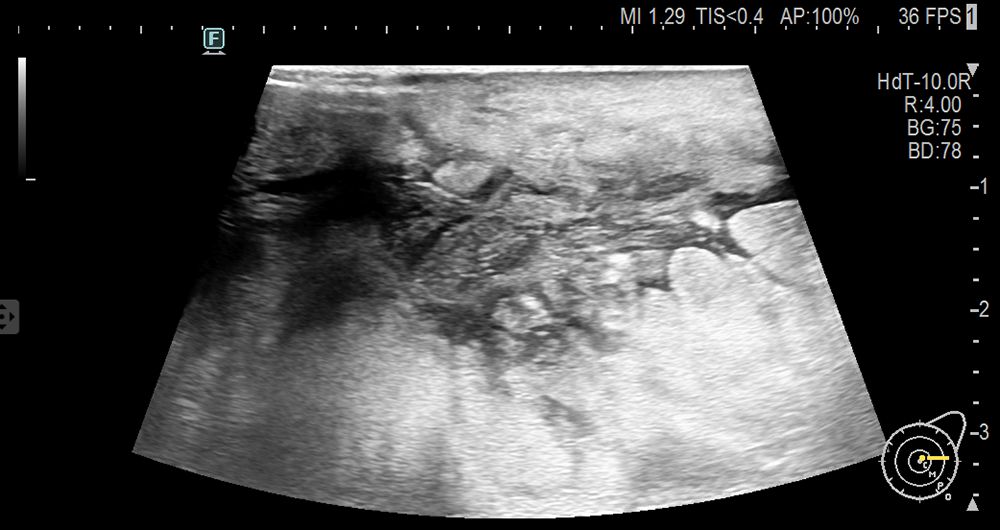

A 51-year-old postmenopausal woman presented with a two-month history of a progressively enlarging, painful mass in her left breast. Initially diagnosed as non-lactational mastitis at a local hospital, she received topical and systemic antibiotics without improvement. Ultrasound imaging at two different hospitals described an irregular hypoechoic mass with partial liquefaction, suggestive of inflammation. The lesion enlarged, developed ulceration, and was accompanied by skin changes. On presentation to our institution, physical examination revealed diffuse breast induration, a 3 × 3 cm ulcerated area with bloody discharge, and axillary lymphadenopathy. Laboratory results revealed elevated inflammatory markers (CRP 53.4 mg/L), mild thrombocytopenia, and significantly elevated serum LDH (3902 U/L). Ultrasound revealed a large, irregular hypoechoic area in the glandular layer of the left breast, partially extending to the skin, with unclear borders and partial anechoic liquefaction (Figure 1).

Ultrasound image showing internal anatomy with varying shades of gray, black, and white patterns representing different tissues. On-screen indicators display technical data like depth and frequency settings.

Figure 1. Ultrasound of breast tumor.